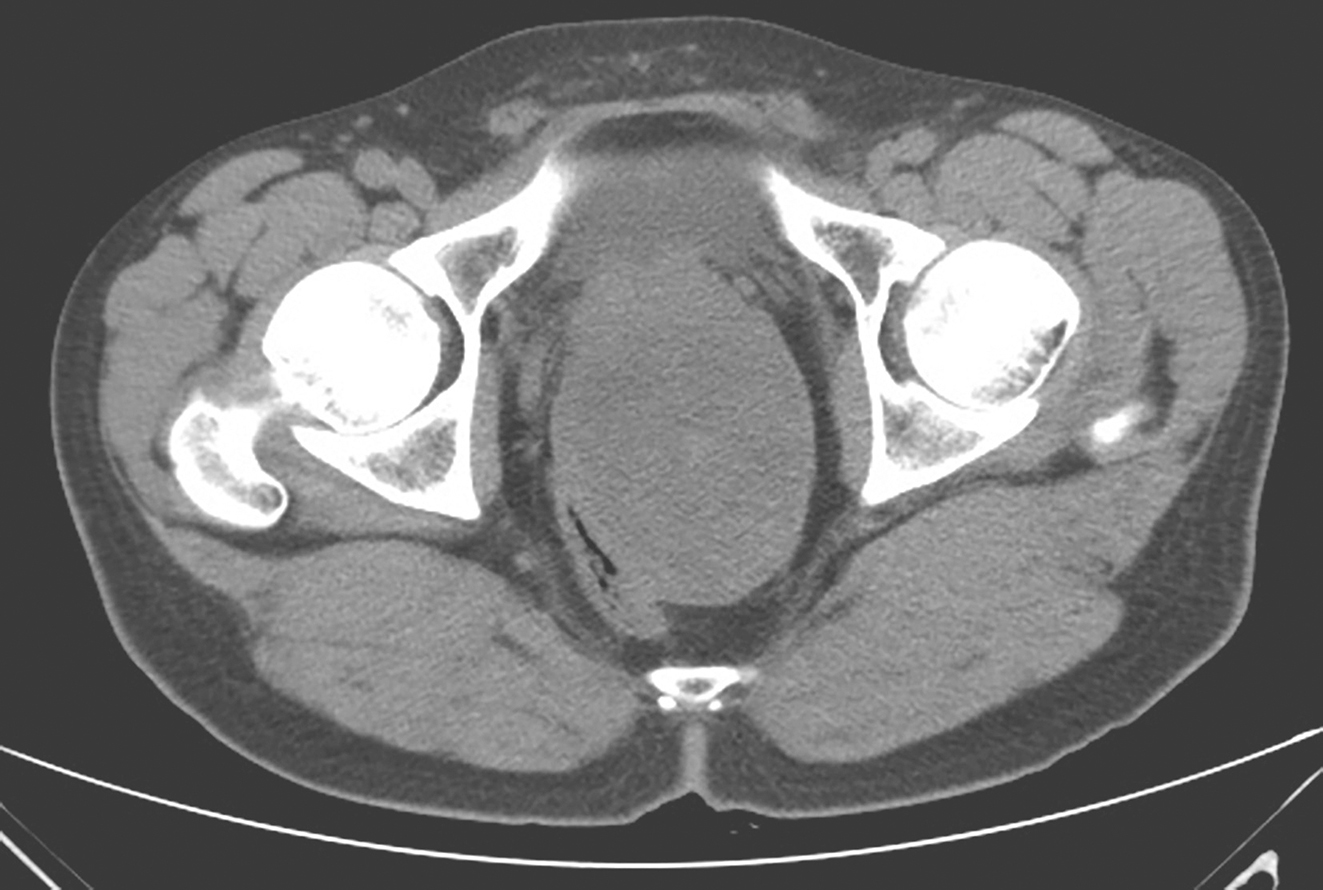

从2017年4月10日起,开始口服甲磺酸伊马替尼400mg/d。服药后每月复查盆腔MRI,示肿瘤无明显变化。考虑患者术前伊马替尼靶向治疗2月余,肿物仍无明显缩小,患者系c-KIT外显子9突变,该型突变对伊马替尼反应欠佳,建议患者增加剂量至600mg/d。患者遵医嘱于2017年6月28日开始加量。伊马替尼加量后2个月复查盆腔MRI,示肿物大小较前仍无显著变化(Choi标准:SD状态)。加做腹盆腔增强CT:盆腔内直肠膀胱窝见一巨大类椭圆形实性肿物,考虑GIST或其他间叶源性肿瘤,肿物边缘光滑,可见包膜,与精囊、前列腺及直肠分界不清,肿物大小约11.7cm×8.9cm,密度欠均匀,内见条片形稍高密度影及散在钙化灶(图2)。

图2 经伊马替尼术前治疗5个月后CT表现